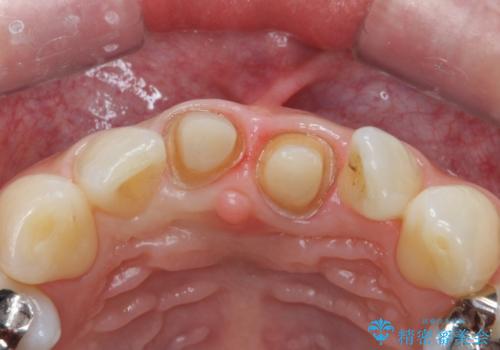

- 前歯の変色とガタつきがきになるとのことで来院されました。

矯正治療の希望はなかったため、セラミッククラウンで被せて治療していくことになりました。

元々根管治療がされていたにも関わらず被せ物が作られておらず、このままではどんどん変色が進んでいってしまう状態でした。

歯をある程度削ることにはなりますが、被せ物にすることで歯の変色を隠し短期間でキレイな口元に仕上げることができました。